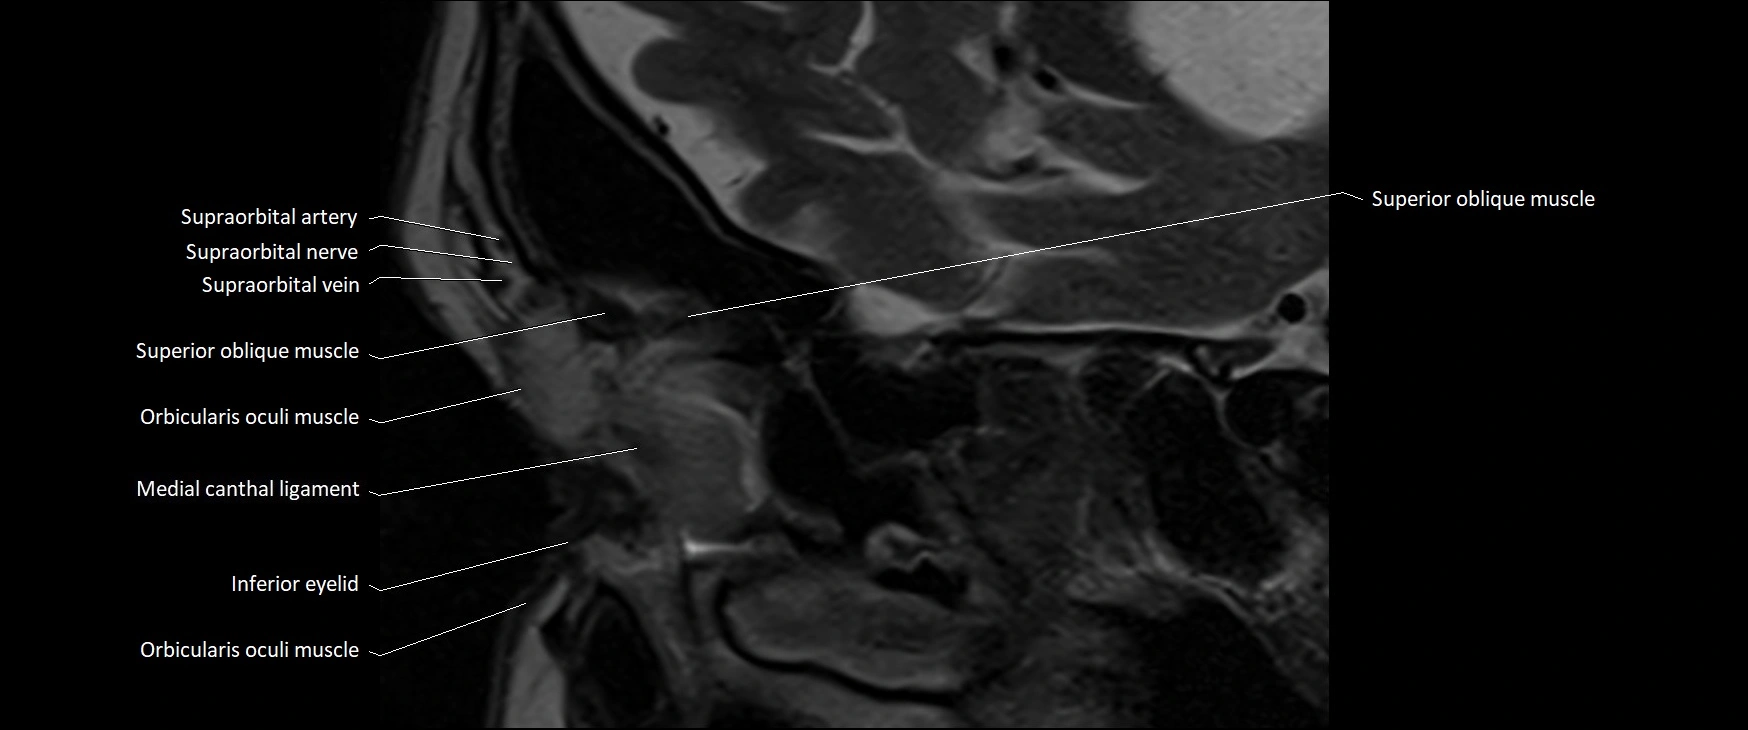

- Inferior eyelid

- Medial canthal ligament

- Orbicularis oculi muscle

- Superior oblique muscle

- Supraorbital artery

- Supraorbital nerve

- Supraorbital vein